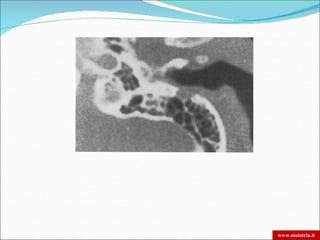

 TC: osteolisi dell’osso timpanico e della base cranica

OTITE ESTERNA MALIGNA DIAGNOSI  Tampone auricolare  Glicemia e VES  TC: osteolisi dell’osso timpanico e della base cranica  RM: invasione dei tessuti molli e dei forami nervosi. Meningite  Scintigrafia:  Al Gallio: + sensibile e specifica per osso e tessuti molli, ma minore risoluzione spaziale zone di diffusione meno esatte  Al Tecnezio99: si fissa sulle zone osteogeniche della distruzione osseea. La sua negatività conferma la guarigione. www.otoiatria.it